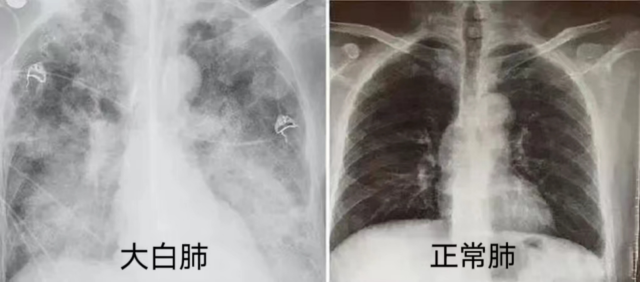

我“阳康”了,能立马做医美手术吗?梁雨晴表示,新冠病毒直接入侵人体呼吸道,造成气道炎症,肺功能不同程度受损,麻醉手术中极易出现气道高反应,低氧血症、通气困难等风险。

新冠病毒累及肺部,表现为不同程度的肺部炎症,会引起肺通气和换气功能障碍,导致低氧血症的发生。